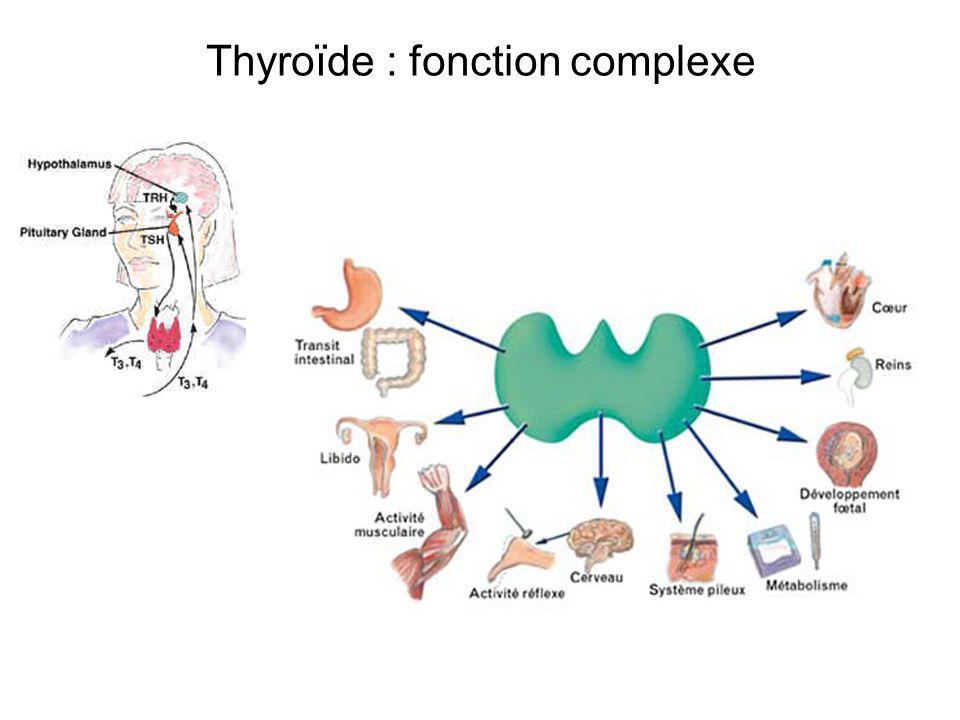

Inscrit le: 12.Fonction thyroïde : sécrétion hormonale La glande thyroïde produit essentiellement la thyroxine ou tri-iodo-thyronine (T4) et la tri-iodo-thyronine (T3) qui circulent dans le sang et jouent un rôle crucial dans le fonctionnement cellulaire.Les hormones thyroïdiennes affectent de nombreuses fonctions vitales de l’organisme, comme la fréquence cardiaque, la vitesse à laquelle les calories sont brûlées, l’intégrité de la peau, la croissance, la production .C'est une inflammation chronique provoquant une infiltration de la thyroïde avec à terme une destruction des cellules de la thyroïde et l'apparition d'une hypothyroïdie ; Thyroïdite du post-partum : une . Nouvelle consultation, nouvelle prise de sang qui révèle un taux de TSH (thyréostimuline) élevé.1 - Un virus qui passe du nez à la thyroïde. La conséquence directe est une production excessive d’hormones thyroïdiennes.

L’hypophyse produit la .La fonction de la thyroïde est de produire les hormones triiodothyronine (T3) et thyroxine (T4) et les cellules C, qui contribuent à réguler, entre autre, le taux de calcium dans le . Mes anti-corps anti-thyroglobuline et anti-thyroperoxydase sont . El Ansari

Physiopathologie.Le rôle de la thyroïde est de : Garantir le bon fonctionnement du système nerveux. La mise en évidence de certaines thyroïdites passe par la recherche des anticorps anti-thyroglobulines (détectés par la technique d'agglutination des globules rouges), et des anticorps anti-thyroperoxydases (anti-TPO ou anti-microsomiaux). La thyroïde sécrète des hormones dont le rôle principal est de réguler le métabolisme du corps (la façon dont il utilise les éléments fournis par l’alimentation et la respiration).L’hyperthyroïdie correspond à une hyperactivité de la glande thyroïde.

agit en synergie avec les hormones thyroïdiennes au niveau des récepteurs cellulaires. Découvrez en quoi consiste l’hyperthyroïdie. La glande thyroïde, située dans le cou devant la trachée, pèse environ 30 g quand il n'existe pas de pathologies associées, et sécrète des hormones thyroïdiennes sous l'action d'une hormone hypophysaire : la thyréostimuline (TSH).06 décembre 2023.

Thyroïde : rôle, fonction et déréglement